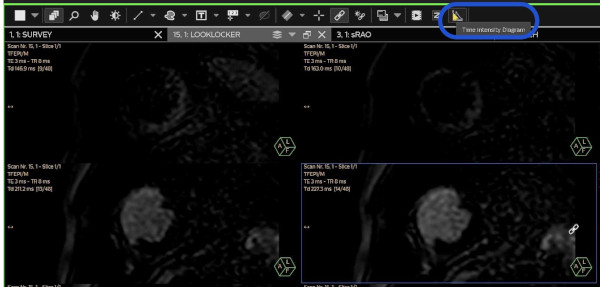

Suche im Look-Locker das beste Bild mit Myokard schwarz und Blut weiss. Klicke dann auf Time Intensity Diagram.

Wähle im *Draw Roi Menu* die *Freehand Contour* aus

Zeichne ein Roi ins schwarze Myocard und klicke anschliessend auf Show Grap

Die dazugehörige Zeit-Intensitätskurve erscheint

hier kannst Du kontrollieren, ob die TI-Wahl einigermassen richtig war. Es ist nicht unbedingt der tiefste Wert der Richtige. Es hängt auch vom Kontrast zwischen Myokard und Blutsignal ab !